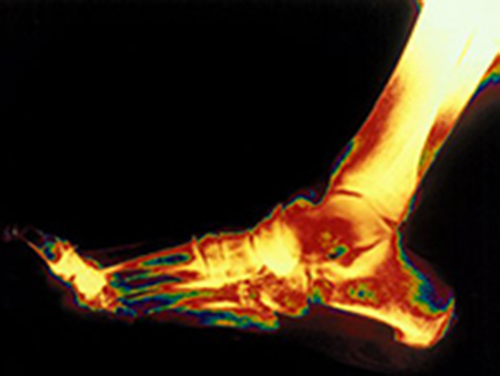

Восстановление хрящевой ткани поможет предотвратить остеоартрит

А значит, исчезнет необходимость в замене сустава - эндопротезировании. Эта операция повышает риск сердечного приступа, сообщает The Times of India. По словам специалистов, за последние 20 лет было разработано много новых методов.

К ним относится, например, пересадка хрящевой ткани. Эта операция бывает одноступенчатой и двухступенчатой. Ученые говорят: особенно важно восстанавливать хрящевую ткань у молодых людей. В целом данное направление активно развивается. Например, в Индии недавно появился клуб, который займется продвижением методов восстановления хрящевой ткани и регенеративной медицины в стране.

Кстати, недавно группа инженеров нашла замену для чернил в трехмерной биопечати. Эта замена поможет получить "хрящевые пластыри", которые решат проблему изношенных суставов. Хрящевая ткань удобна для печати. Она состоит из одного типа клеток и не имеет кровеносных сосудов.